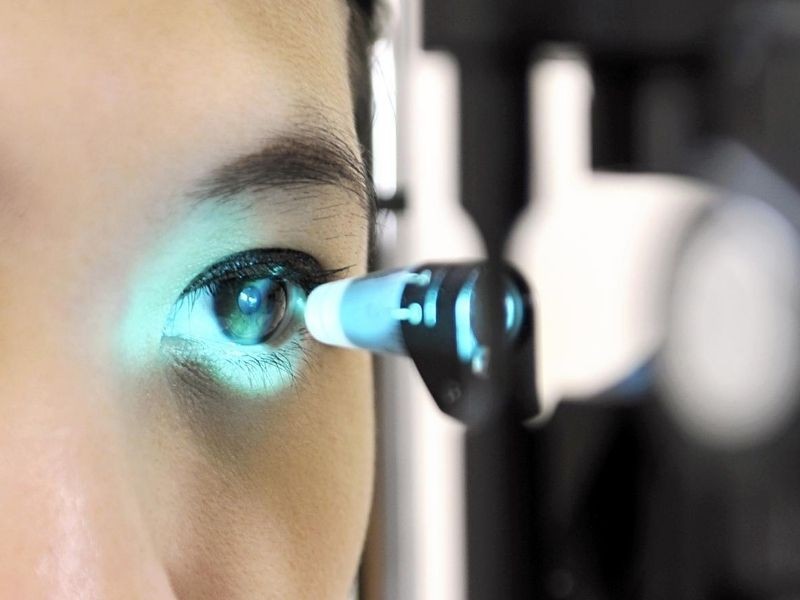

Tonometria: A pressão intraocular é medida utilizando um tonômetro, que pode ser de aplanação (Goldmann) ou de sopro (não-contato), dependendo do protocolo e das necessidades do paciente.